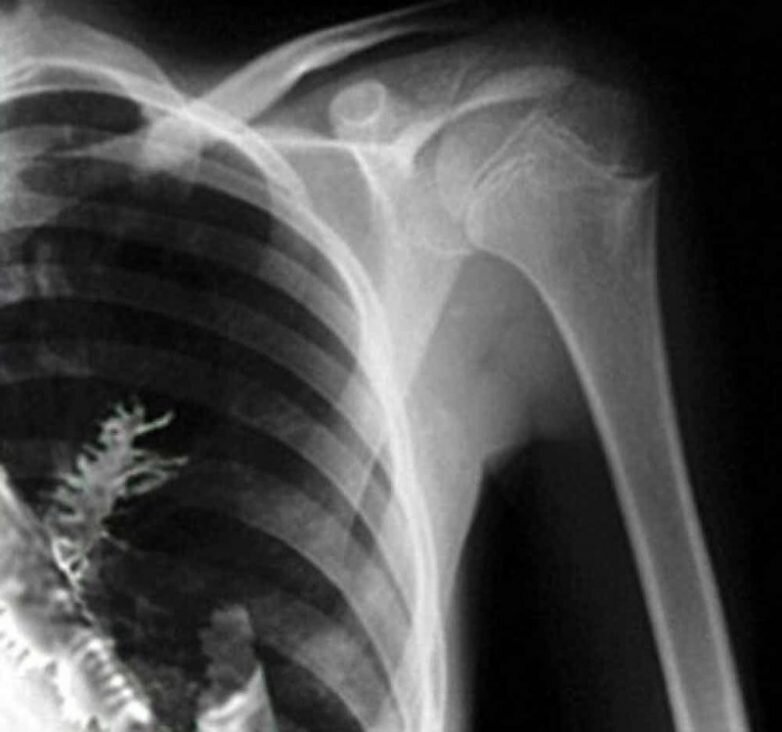

Это случается не часто, но семена могут действительно расти внутри вас. 28-летний русский, приехавший в больницу с жалобой на боль в груди, был поспешно оперирован, когда врачи обнаружили 5 см ели, растущей в его легком. А в Массачусетсе 75-летний мужчина тоже лечился от роста в легком, после того, как гороховое семя в его еде упало не в ту трубку.